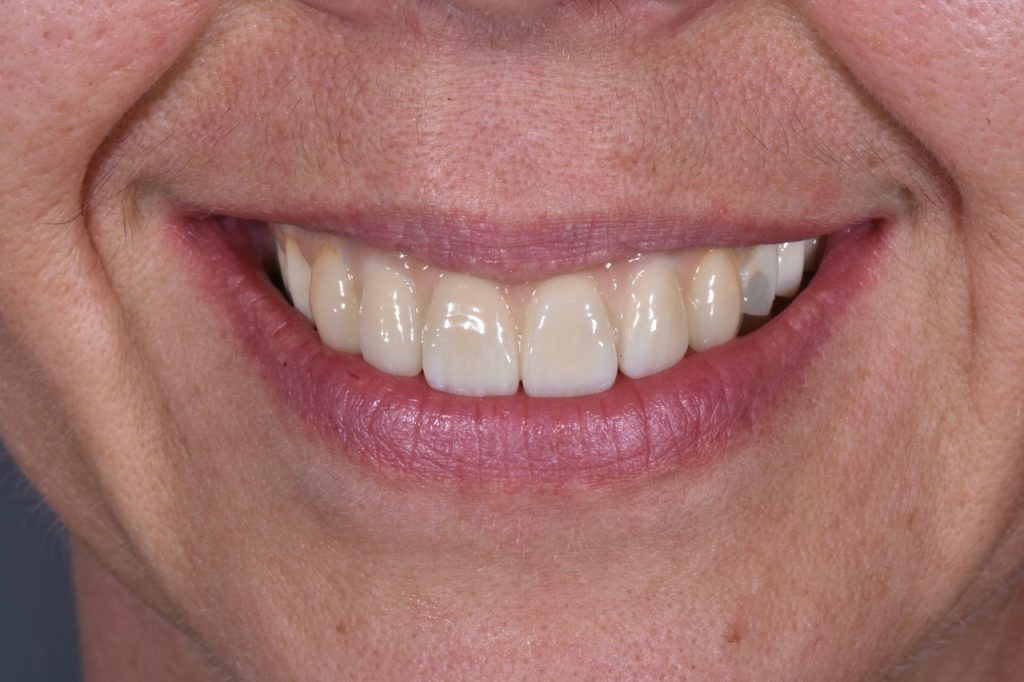

Les implants visent à remplacer une ou plusieurs dents absentes

La chirurgie guidée permet de poser les implants à l’aide d’un guide, ce qui rend la chirurgie plus sure et précise, elle permet de proposer la mise en place de provisoires immédiatement le jour de la chirurgie sir la stabilité de l’implant le permet.